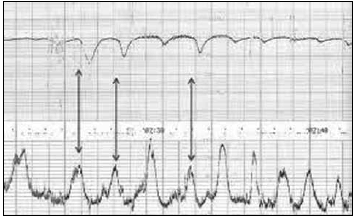

No mesmo momento do toque, foi realizada a seguinte cardiotocografia.

Com base nesse traçado, quais são a classificação e a conduta?